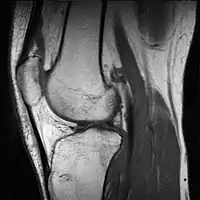

МРТ опорно-рухового апарату

Діагностика захворювань опорно-рухового апарату включає МРТ хребта, діагностику захворювань суглобів і пухлин м′яких тканин.